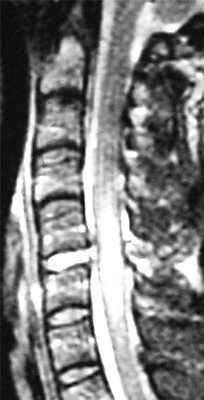

Особую категорию составляют пациенты, у которых, несмотря на наличие неврологической симптоматики, не выявляется изменений при рентгенографии или КТ. Число таких пациентов составляет около 10%. Среди различных механизмов подобных травм наиболее вероятна кратковременная компрессия спинного мозга задней продольной связкой и дисками, либо, жёлтой связкой и пластиной дуги. Посколько резкие сгибания и разгибания наблюдаются при высокой подвижности в сегментах, такие травмы более вероятны в шейном отделе позвоночника. Спондилолиз усугубляет эту ситуацию, приводя к центральному синдрому спинного мозга. В этих случаях необходимой является МРТ позвоночника. Характерными находками, которые мы часто видим при травмах при МРТ в СПб, являются отёк спинного мозга и гематома, причём последняя при МРТ позвоночника плохим прогностическим фактором в отношении восстановления неврологического дефицита. К наиболее тяжелым осложнениям шейной травмы относится расслоение магистральных артерий, определяемое по МРТ, МРА или КТ и КТА. В высоком поле такой вид травм лучше виден чем в открытом МРТ. МРТ СПб позволяет выбирать место МРТ, однако, острая травма шейного отдела позвоночника требует высокоспециализированного нейрохирургического отделения

МРТ шейного отдела позвоночника. Острая травма. Компрессия спинного мозга, отек и контузия. Сагиттальная Т2-взвешенная МРТ.

МРТ шейного отдела позвоночника. Т2-взвешенная сагитальная МРТ. Острая травма с повреждением задних элементов позвонков и отеком спинного мозга.

МРТ шейного отдела позвоночника. Острая травма. Отёк спинного мозга. Сагиттальная Т2-взвешенная МРТ.